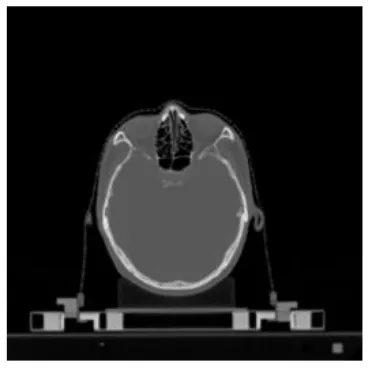

| Input CT image | Organs with manual segmentation | Organ with automatic segmentation | |

| Brainstem | ![]() | ![]() | ![]() |

The result of manual and automatic organ segmentation.